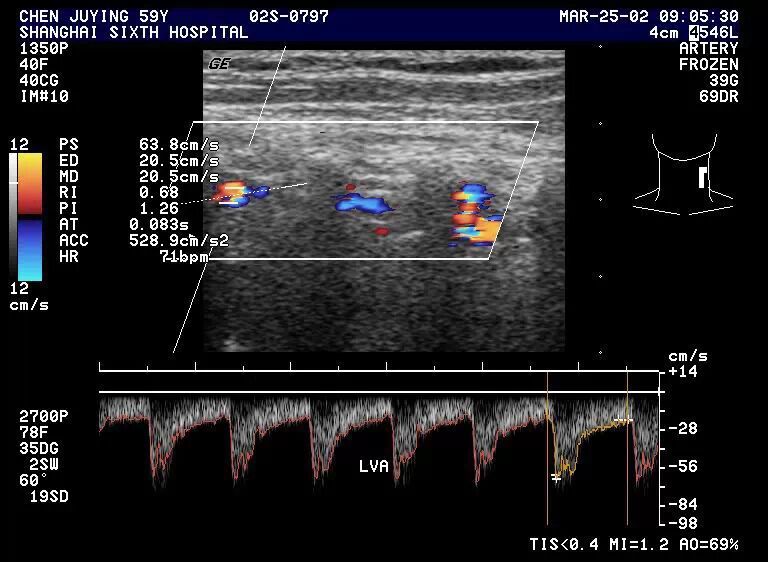

2.频谱多普勒  椎动脉血流频谱与颈内动脉相似,但流速比颈内动脉低。

1.5 正常椎动脉频谱